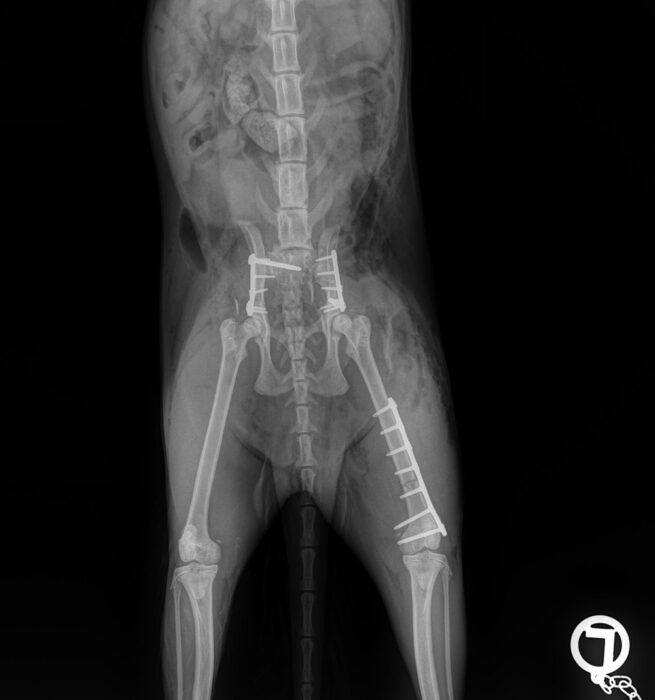

This one-day practical course focuses on the TTA Rapid procedure for cruciate repair, including techniques for addressing patella luxation concurrently.

Geared towards veterinarians interested in mastering the TTA Rapid technique, this practical course includes sawbones and wet lab sessions for hands-on learning. Participants will discuss diagnosing cruciate ruptures, preoperative planning, surgical guidelines, and potential complications and solutions. The course will also explore unique methods for treating patella luxation simultaneously, providing ample opportunities for questions and hands-on practice.

- Pre operative planning for TTAR procedure

- Treating Patella Luxation in conjunction with cruciate surgery

Cranial Closing Wedge Surgery

Practical Forelimb and Hindlimb Fracture Repair (2 day course)

Locking Plating - Advanced Fracture fixation with the LeiLOX System (2-day course)